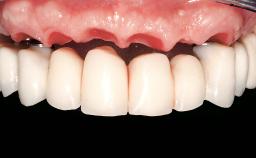

Immediate Loading of Eight Implants in the Maxilla and Six Implants in the Mandible and Final Restoration with Three-Unit and Four-Unit FDPs

Prosthesis Type FDP

SAC Level Complex

Defining Characteristics Fully edentulous upper jaw to be rehabilitated with an implant-borne fixed dental prosthesis

Loading Protocol Immediate

Esthetic Risk High